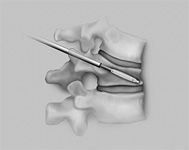

- In sehr speziellen Fällen kann das Bandscheibenmaterial rein endoskopisch entfernt werden.

- In allen anderen Fällen wird durch einen kleinen Hautschnitt von 2-3 cm der Wirbelkanal dargestellt.

- Unter dem Operationsmikroskop wird der Nerv weggehalten und das herausgesprengte Bandscheibenmaterial entfernt.